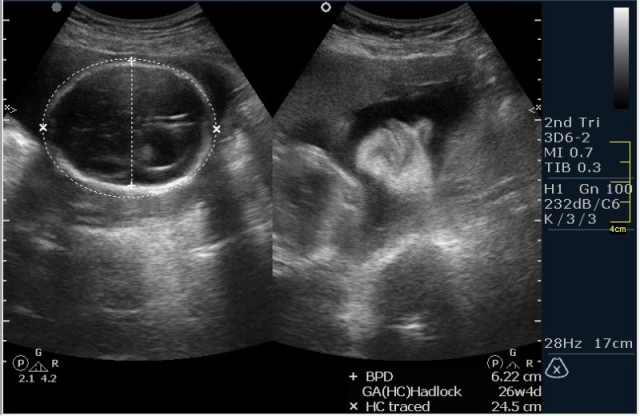

1.Вентрикуломегалия/гидроцефалия (на сонограмме №1 размер задних рогов боковых желудочков 16мм при норме до 10 мм включительно;

На сонограммах головы плода визуализаируется гифдроцефалия, патогенетически связанная со спинномозговой грыжей (менингомиелоцеле) представленная в 2D и 3D режимах. В режиме Skeleton не удалось получить "картинку презентационного качества", плод начал сильно вертется; но рекоммендация очень грамотная :idea: , спасибо за ваш пост!